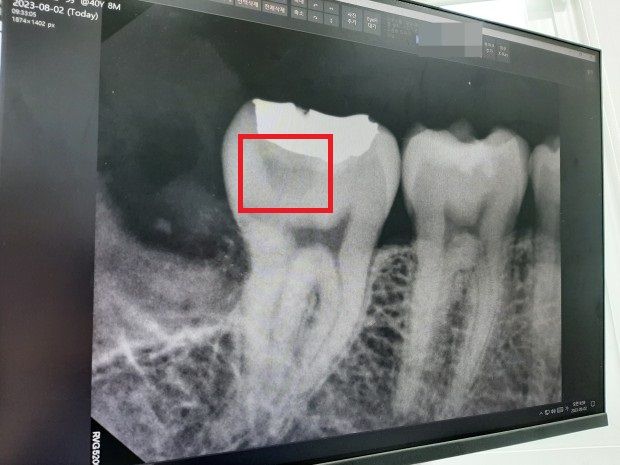

발치 후 사진입니다. (발치하면서 사랑니에 충치 의심 흔적이 있다고 설명해주셨고요.)

3. 어금니 골드 인레이 보철한 아래 부분에 어두운 색이 있는데 이게 충치 의심된다는데 사진 상으로도 충치가 맞을까요? (빨간색 네모로 체크한 부분입니다.)

사실 저 부위는 새로 골드 인레이한지 4년~5년 정도 밖에 안되었거든요. 현재 다른 쪽의 금니는 15년 넘게 써도 멀쩡한데 새로한지 얼마 안된 부위가 충치 의심된다고 하니 정말 그런가 싶어서요.

보철 새로할때마다 치아를 깎아내는게 싫어서 최대한 오래쓰고 싶은데 정말 충치일까요?

4. 보철 새로 안하고 저 빨간색 네모 부분이 충치인지 아닌지 알 방법은 없나요?